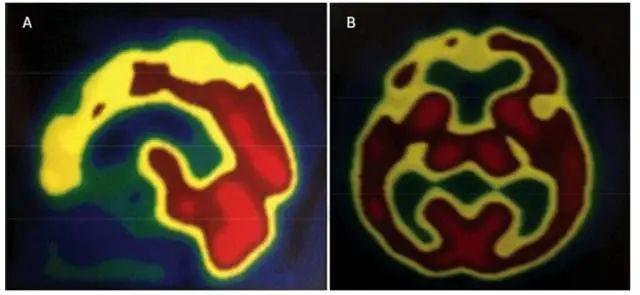

10年前蛛網膜下出血導致右外側額葉損傷(right lateral frontal injury)。中風導致左側尾狀核(left caudate nucleus, LCN)部分受損。

1號病人的大腦fMRI圖。|研究論文